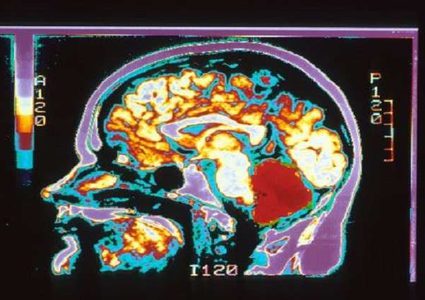

توصل علماء الأعصاب أخيرا إلى سبب مرور الوقت ببطء شديد عندما نشعر بالملل المتكرر. ويعتقد العلماء أن منطقة من الدماغ تسمى "القشرة المخية الأنفية الجانبية" …

وجد باحثو جامعة كاليفورنيا في سان فرانسيسكو (UCSF)، "هدفا فعالا" في الدماغ للتحفيز الكهربائي لتحسين مزاج الأفراد الذين يعانون من الاكتئاب. وتظهر النتائج المنشورة في …

يمتلك دماغ الإنسان ساعتين داخليتين تتنبآن بالمستقبل القريب، وفقا لبحث جديد من جامعة كاليفورنيا، والذي يؤكد أن أسلاكنا العصبية يمكنها أن تتنبأ بأجزاء من الثانية …

أجرى علماء جامعة كامبريدج البريطانية دراسة علمية هي الأكبر والأوسع لمعرفة أوجه الاختلاف بين دماغ الرجل والمرأة، استنادا إلى معطيات لأكثر من 671.6 ألف شخص، …